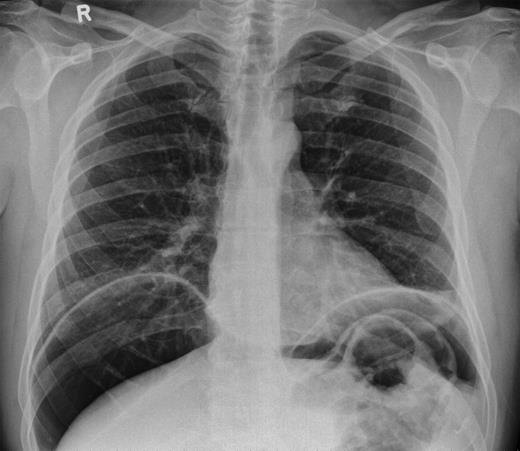

In 2011, a 46-year-old man presented with an acute abdomen. Patient had a 3 day history of abdominal pain with dyspepsia, initially epigastric with pain radiating to his shoulder. He had no associated symptoms of nausea, vomiting or change in bowel habit. There was no history of peptic ulcer disease, inflammatory bowel disease, diverticular disease or malignancy. His pain was refractory to standard analgesics and exacerbated by movement and palpation of the abdomen. There was no past medical or family history of note, and the patient had never experienced these symptoms before. Routine observations were normal, except for tachycardia. On examination, there were no peripheral stigmata of inflammatory bowel disease, abdomen was diffusely tender and tympanic, but soft with normal bowel sounds. Blood tests showed no significant abnormalities, and C-reactive protein (CRP) levels were not measured. Plain abdominal and erect chest radiographs showed pneumoperitoneum (Fig. 1) with Rigler's sign present around small bowel loops lower in the abdomen (Fig. 2).